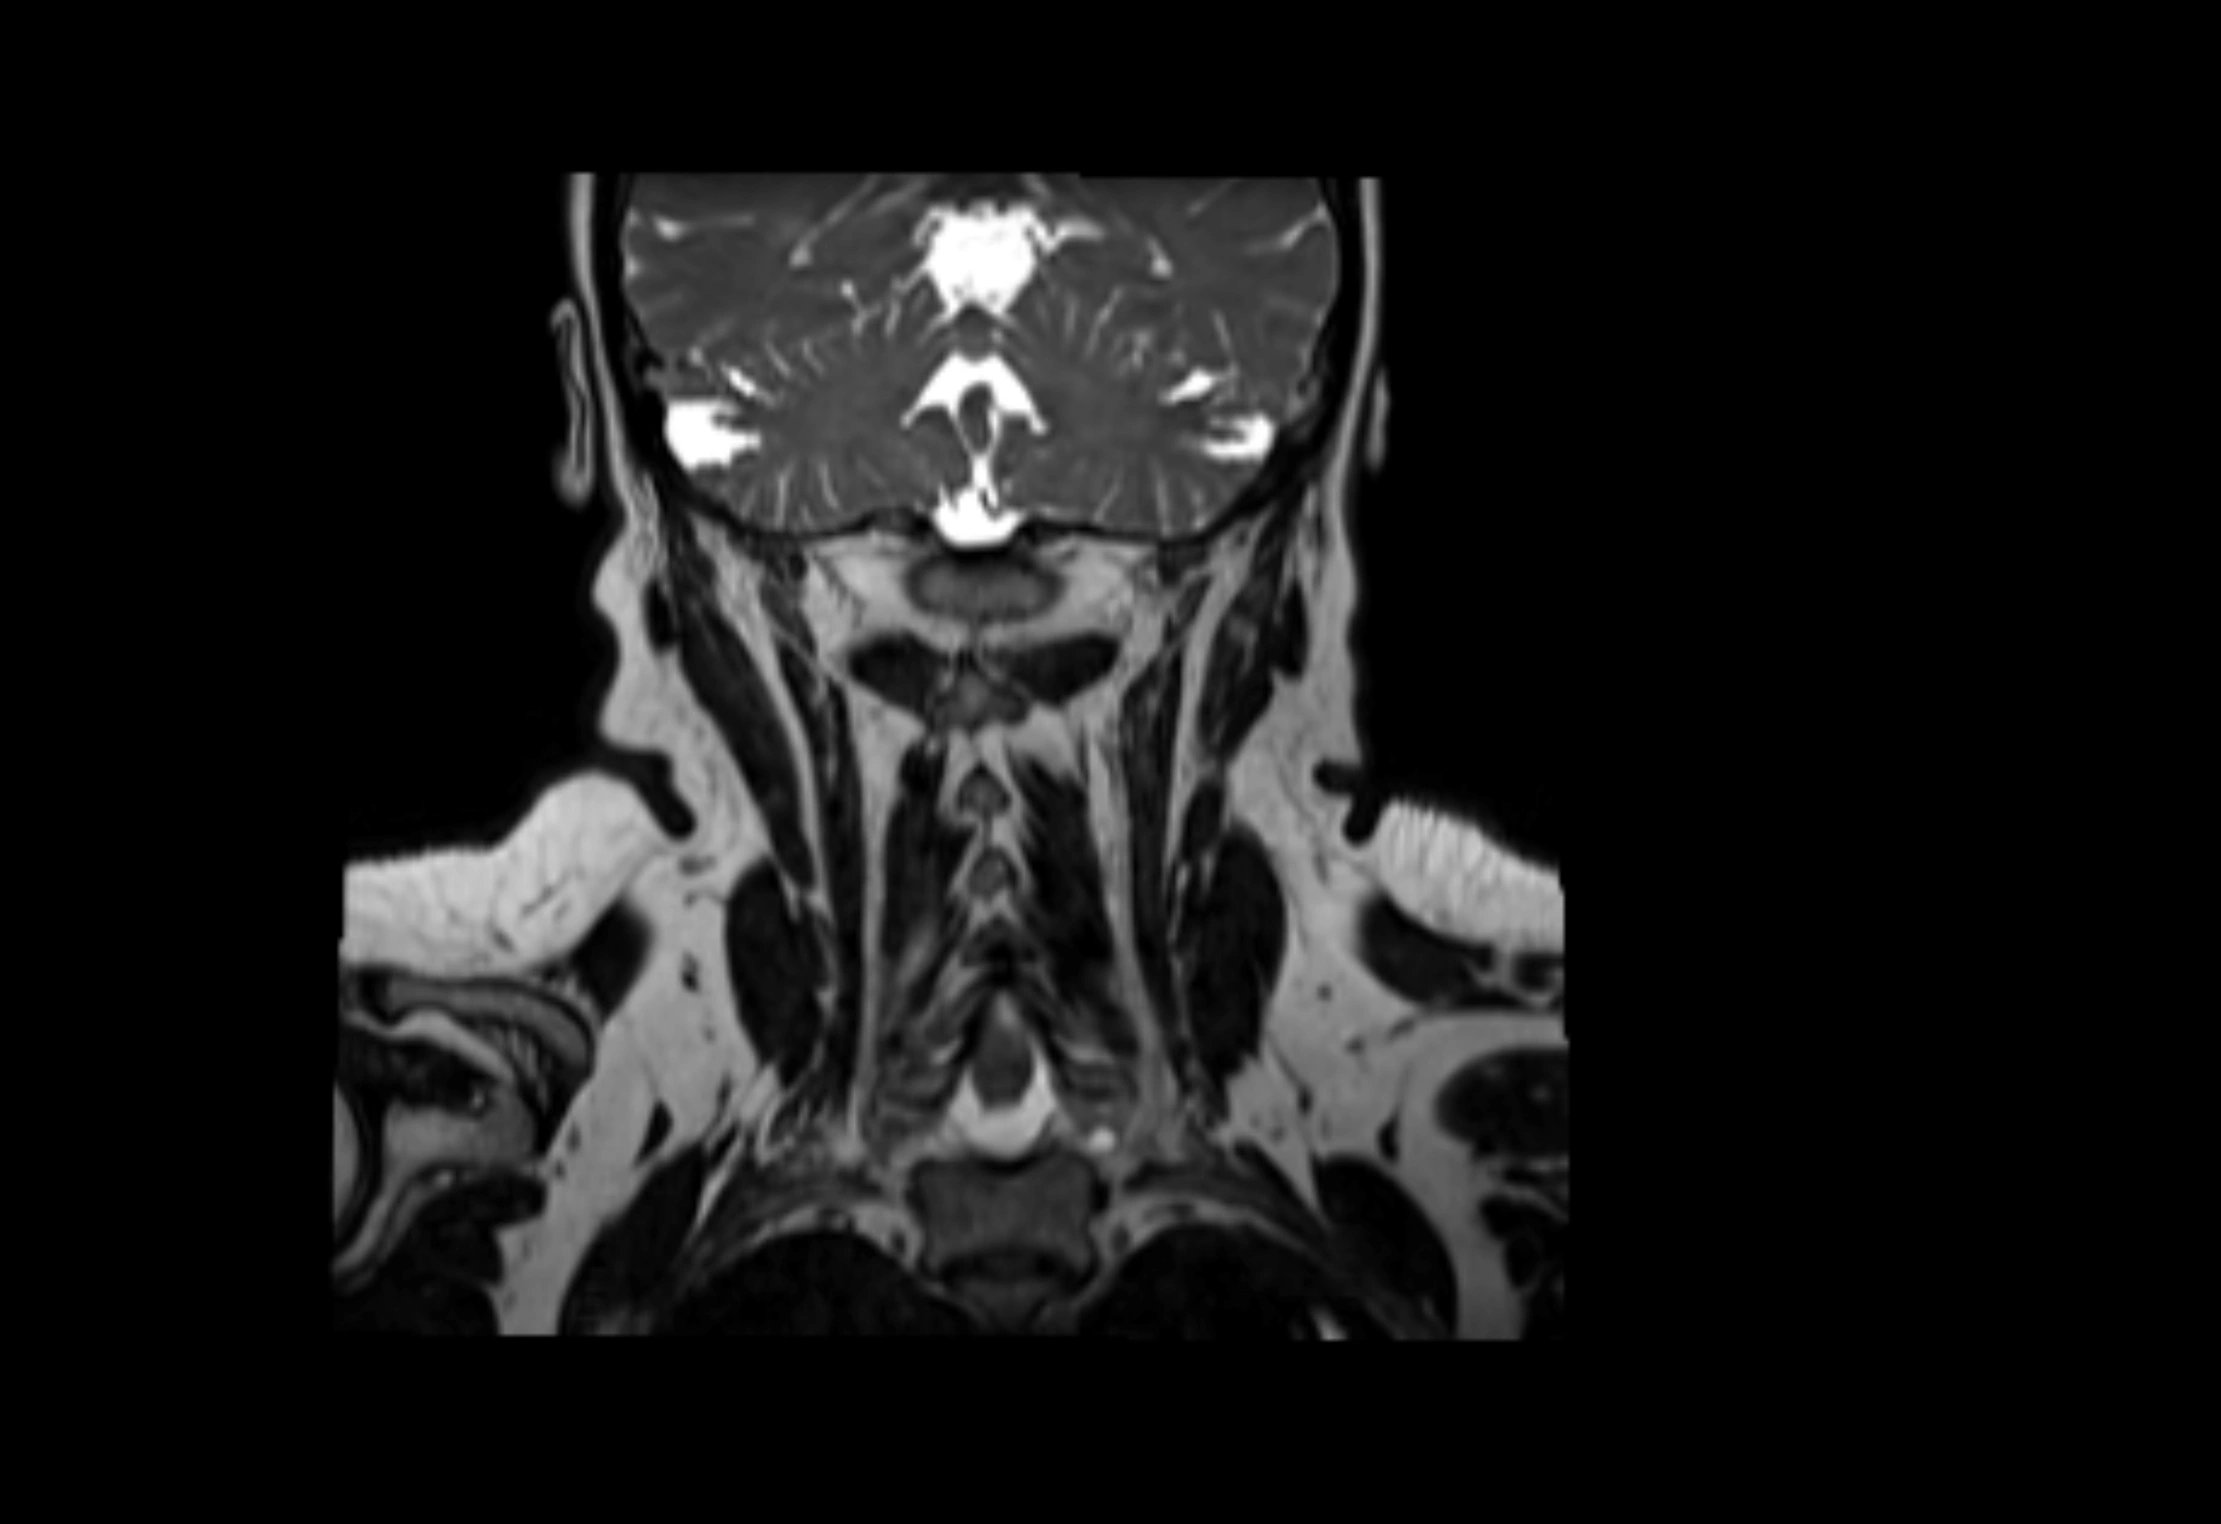

MRI images

image